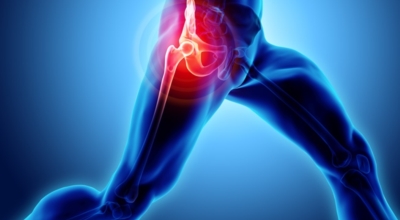

고관절이란 골반을 지탱하는 관절로서 근육과 힘줄로 구성되어 있어요. 학계에서는 고관절을 엉덩이 관절이라고 부르기도 하며 인체의 하중을 지탱하는 아주 중요한 관절입니다. 각별히 고관절은 우리가 정상적으로 서있거나 움직일 수 있게 만들어주며 달리기, 점프, 무거운 무게를 들 때 최대 체중의 2~10배 가량의 하중을 받기 때문에 적절한 관리가 필요합니다. 오늘은 고관절에서 일어날 수 있는 고관절 통증 증상에 관해서 알려드리도록 하겠습니다.

고관절염은 고관절에 나타나는 관절염을 말하며 고관절의 연골이 닳게 되면서 뼈와 뼈가 서로 부딪히며 통증을 일으키게 돼요. 고관절염 초기 증상으로는 사타구니 부위가 불편하게 느껴지며, 무리하면 통증이 발생할 수 있으며, 관절염 증상이 심해지면서 사타구니에서 느끼던 통증이 허벅지와 엉덩이 통증으로 이어지기도 하는데, 고관절염 통증 증상으로 초기에는 허리 통증이 나타나 허리 질환과 혼동하기 쉬우며 각별히 척추질환이 있는 사람은 고관절 통증과 마찬가지로 엉덩이, 다리 통증이 동반되기 때문에 훨씬 헷갈리는 경우가 많습니다.